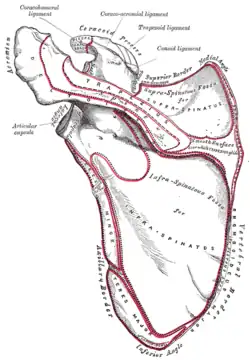

Posterior view showing the relations between teres major muscle (in red) and the other muscles connecting the upper extremity to the vertebral column. | |

Teres major muscle (in red) seen from back (posterior to anterior perspective). | |